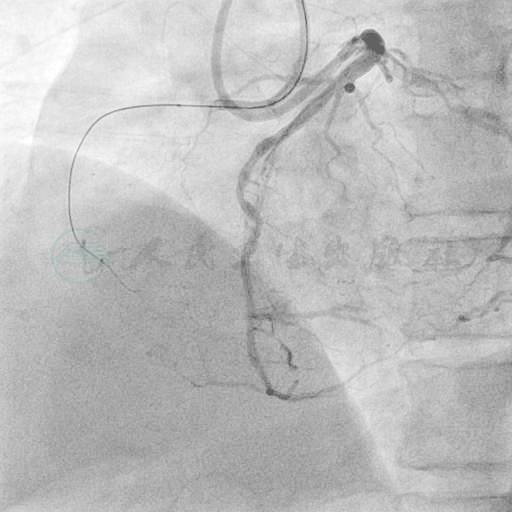

选用右侧桡动脉径路,6F血管鞘。造影发现:右冠状动脉(RCA)近端起完全闭塞,未见自身前向侧支循环供应远端(图5);左主干无严重狭窄,前降支近段至开口90%狭窄,回旋支中段70%狭窄(图6、图7);左冠侧支循环供应右冠远端(图8)。

图5 冠脉造影提示RCA近段起完全闭塞,自身前向未见侧支循环形成